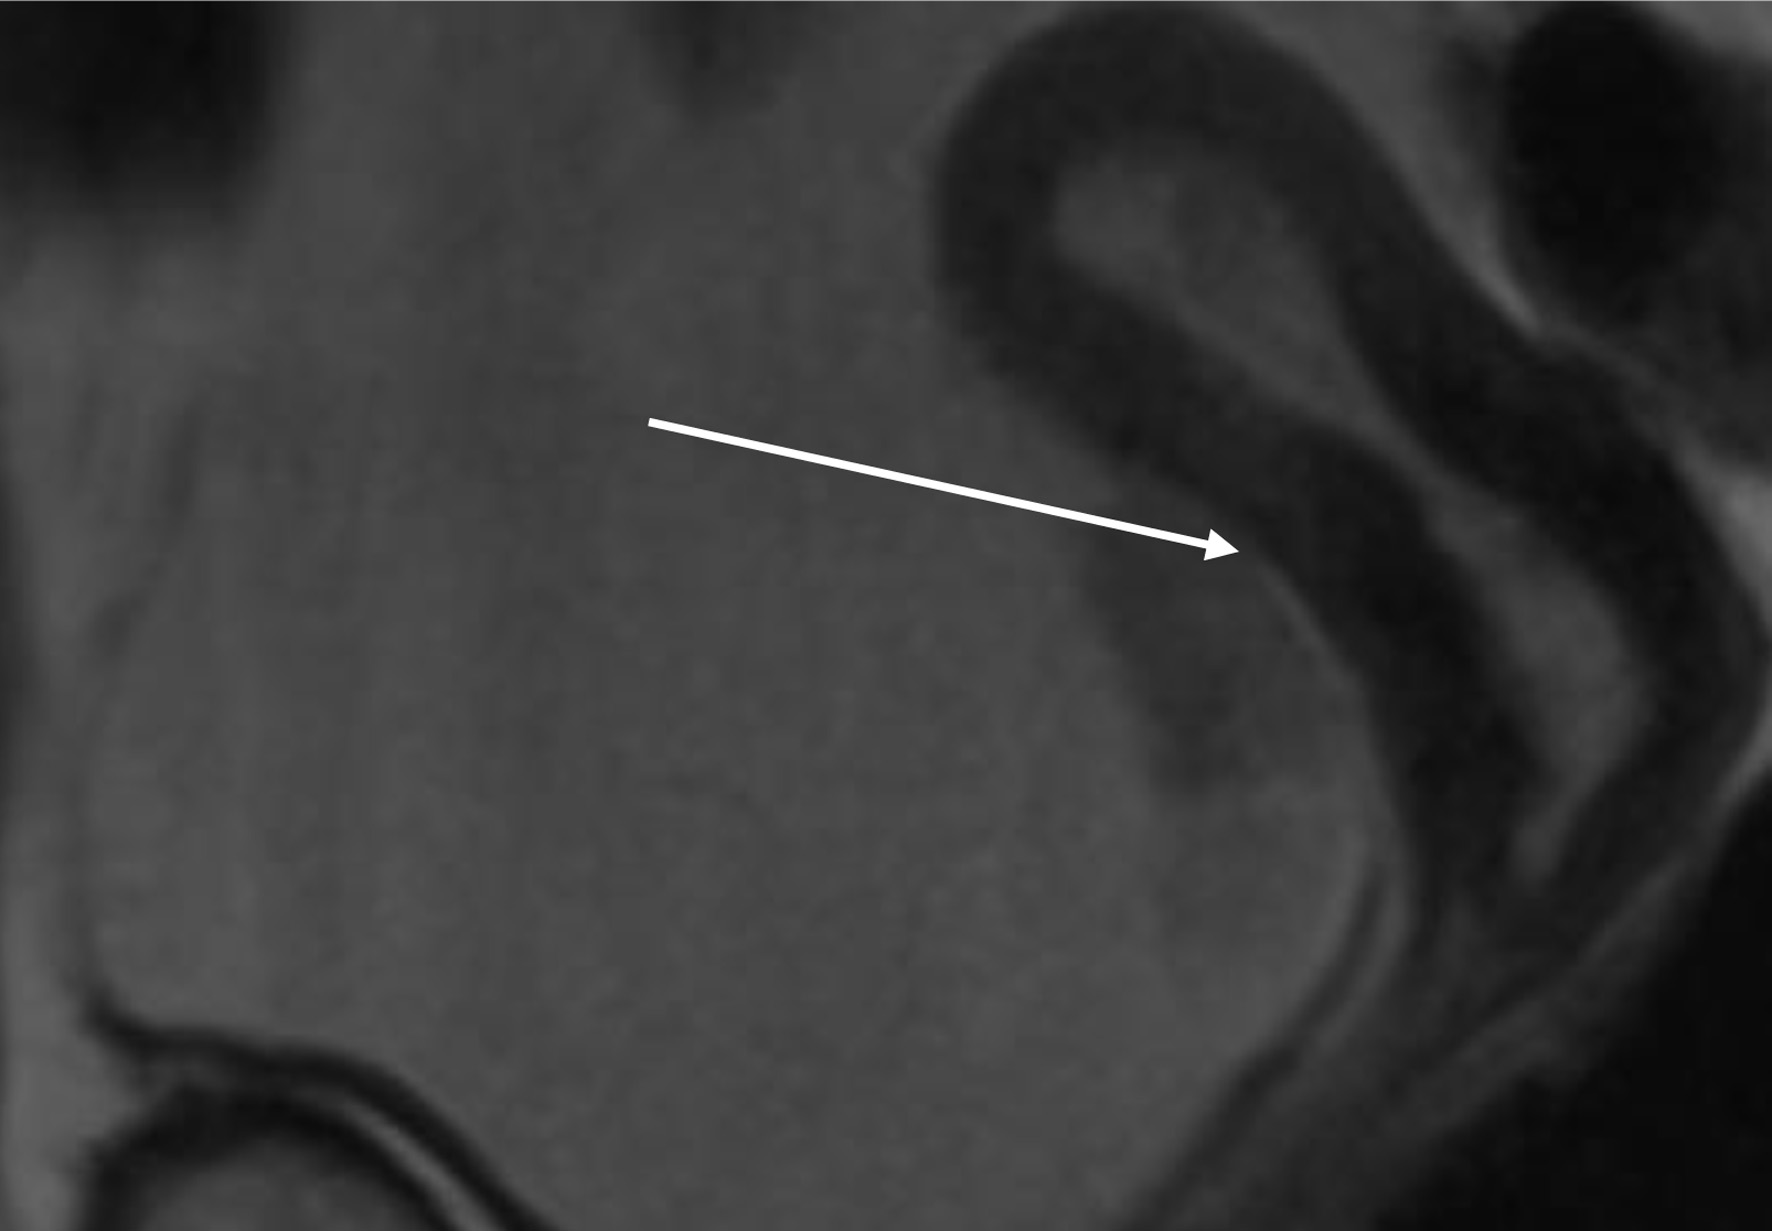

The patient, who had undergone a left nephroureterectomy 1 year earlier for urothelial carcinoma, presented again with suspected malignancy of the right upper urinary tract. Following urological consultation and instrumental evaluation (cystoscopy), urinary bladder tumors were detected, and the patient proceeded to further imaging assessment. Magnetic resonance imaging (MRI) of the upper abdomen revealed a tumor in the right kidney with invasion of the ureter and perirenal adipose tissue (Figs. 6 and 7). Lower abdominal MRI examination confirmed urinary bladder tumors with infiltration of the distal ureter and uterus (Figs. 811). Considering the patient’s clinical status, the potential aggressiveness of the malignancy, the absence of definitive histopathological confirmation of the new tumors (which could represent distinct lesions requiring separate pathological sampling), and the patient’s preference, no preoperative neoadjuvant therapy was administered. Surgery was therefore the only available therapeutic option, to which the patient provided full informed consent, despite her high-risk clinical profile and the complexity of the proposed high-risk surgical procedure. The postoperative histopathological report demonstrated high-grade renal urothelial carcinoma with contiguous extension to the ureter, urinary bladder, and bladder neck. Five of the 11 excised lymph nodes were metastatic, classifying the tumor as pT4N2Mx. Despite radiological evidence suggestive of uterine involvement, histopathological examination of the uterus and ovaries showed no malignancy; instead, polypoid endometrial hyperplasia and ovarian cysts were identified.

Figure 6. Lower abdomen magnetic resonance imaging (MRI) examination demonstrated tumor invading ureter (arrow).

Figure 7. Upper abdomen magnetic resonance imaging (MRI) examination demonstrated tumor invading renal parenchyma (arrow).